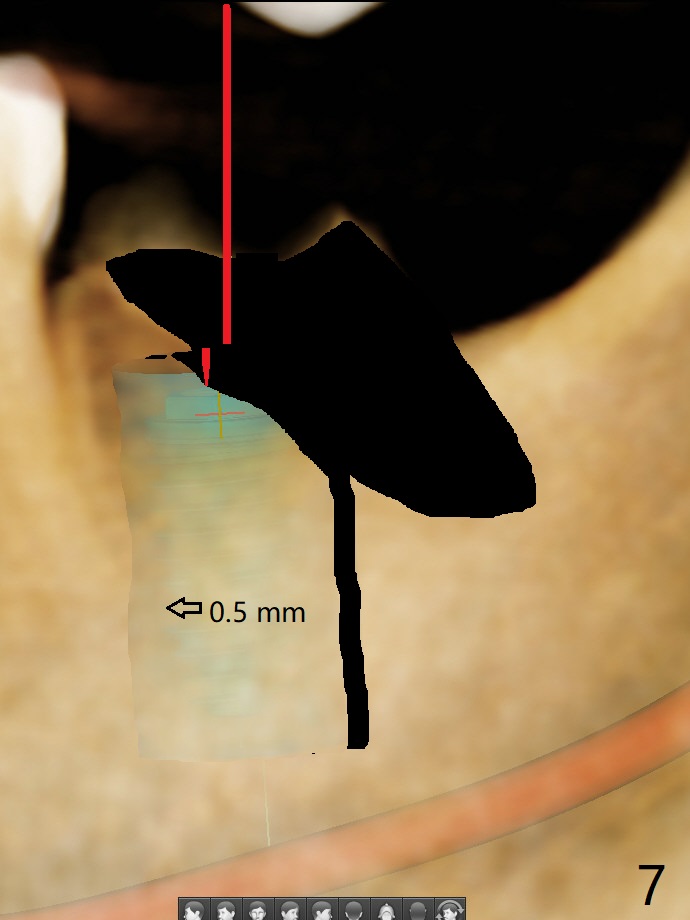

56岁女右侧不好咀嚼,右下7远中龈下龋齿(图一,二),能保留吗?Implant or rct plus crown lengthening, either way is fine, but implant may be more straightforward (Robert). Hi, Jennifer: I love the way you design implant in the mesial slope of the lower 2nd molar (Fig.1,4). When I place an implant free hand, I make sure that the long axis of the implant is 5 mm from the distal surface of the 1st molar (half of the mesiodistal width of the 2nd molar, Fig.5) as long as the implant is not too close to the neighboring root (black dashed line of Fig.5). PAs are taken several times intraoperatively to monitor the distal drifting (Fig.6 open arrow) of the osteotomy (red line). In my opinion, the drifting exists with guided surgery, especially the change of angulation. Can you intentionally move the implant mesially (Fig.7 open arrow) by 0.5-1 mm depending upon bone density or tilt the implant mesial coronally? Thanks for your consideration.